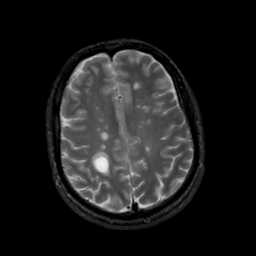

MR Study #5, March 10, 1991 -- Slice #37